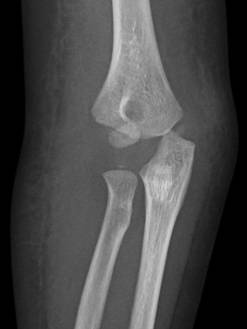

這題的關鍵在於辨識兒童肘部X光片上,遠端肱骨外側髁(capitellum)的骨折線與移位。4歲兒童的骨化中心發育程度是判讀的重要依據。

兒童肱骨外髁骨折,尤其是移位性骨折,由於其關節內骨折的特性和對生長板的影響,通常需要手術復位及內固定以確保良好的功能和避免併發症。